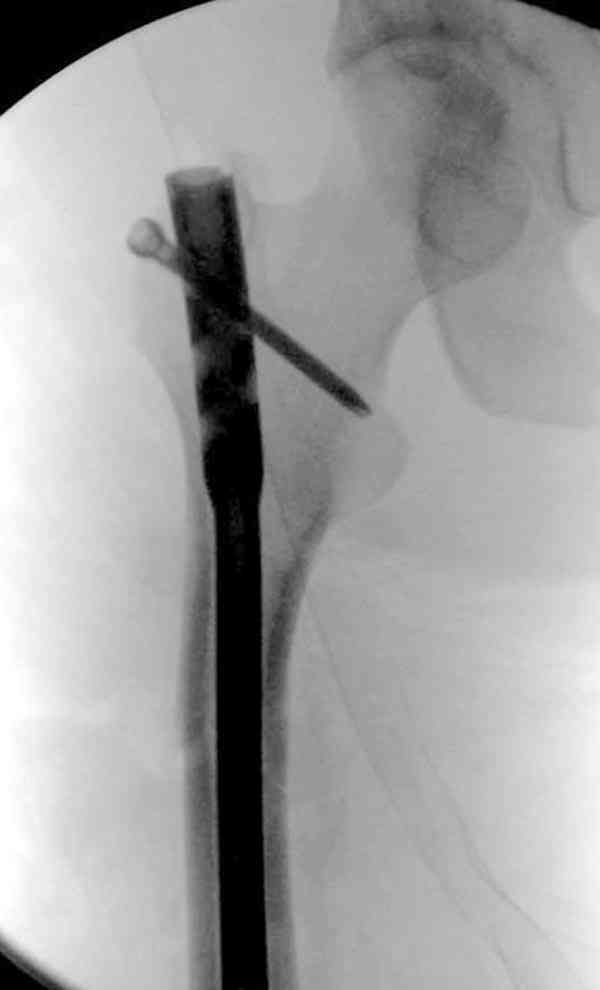

> Вот несколько. С тисками и трубой на днях сделаем.

Саша, последний штифт, пожалуй, перегнули?

> Саша, последний штифт, пожалуй перегнули?

Там заход сделан как для прямого штифта, не через вертел.